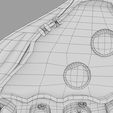

神经肌肉接头示意图